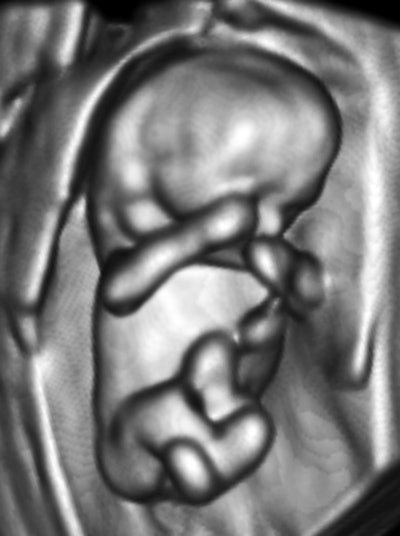

Case 1: Pregnancy, day 64

My own private practice has some routine scanning from local physicians and second-opinion scanning from a much wider geographic zone. Most of the "abnormal NT" cases I used to see were just normal embryos resting supine on the amnion. A recent case was referred from an infertility practice: an 11.2-week embryo thought to have an abnormal NT. This embryo, having a higher specific gravity than amniotic fluid, was dependent in the sac, resting on amnion. Here are an endovaginal view of the neck, an energy Doppler view of the heart, and a 3D survey:

There are multiple cystic hygromas and an apparently normal heart. The 3D really does not look "right" because of a disproportion. No other abnormal findings were evident. We did a cell-free fetal DNA test on maternal blood that established in a few days that this is a case of Trisomy 18.